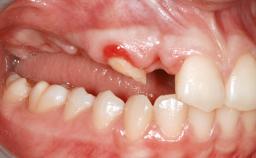

A 45-year-old woman with a completely edentulous maxilla was referred to evaluate the possibility of rehabilitation with an implant-supported prosthesis. This patient was healthy and a non-smoker. She had been wearing a maxillary complete denture opposing a natural mandibular dentition since her twenties. This situation had resulted in progressive resorption of the alveolar ridge, repeatedly creating a need for relining the denture. Twenty years later, despite multiple adaptations and the use of “glues” the denture was unstable and causing the patient psychological and functional discomfort.